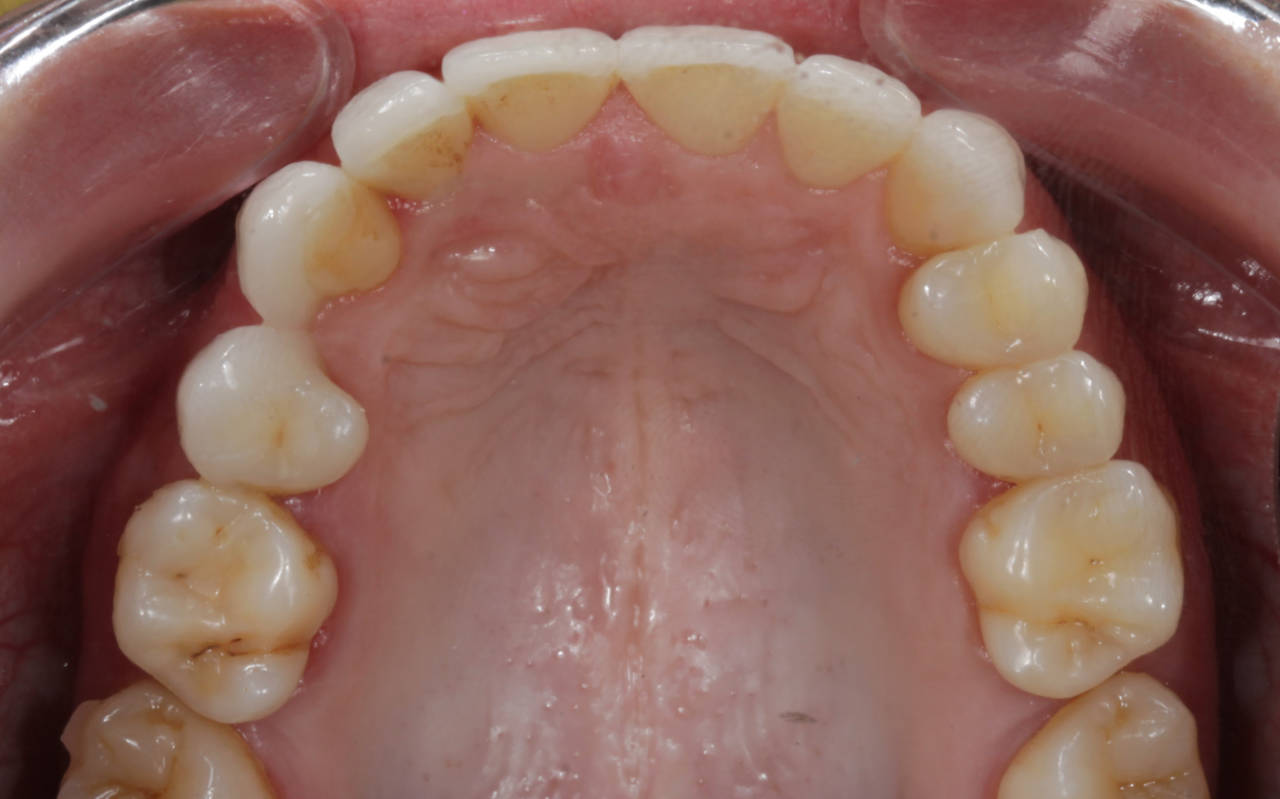

A harmonização do sorriso fez toda a diferença nes